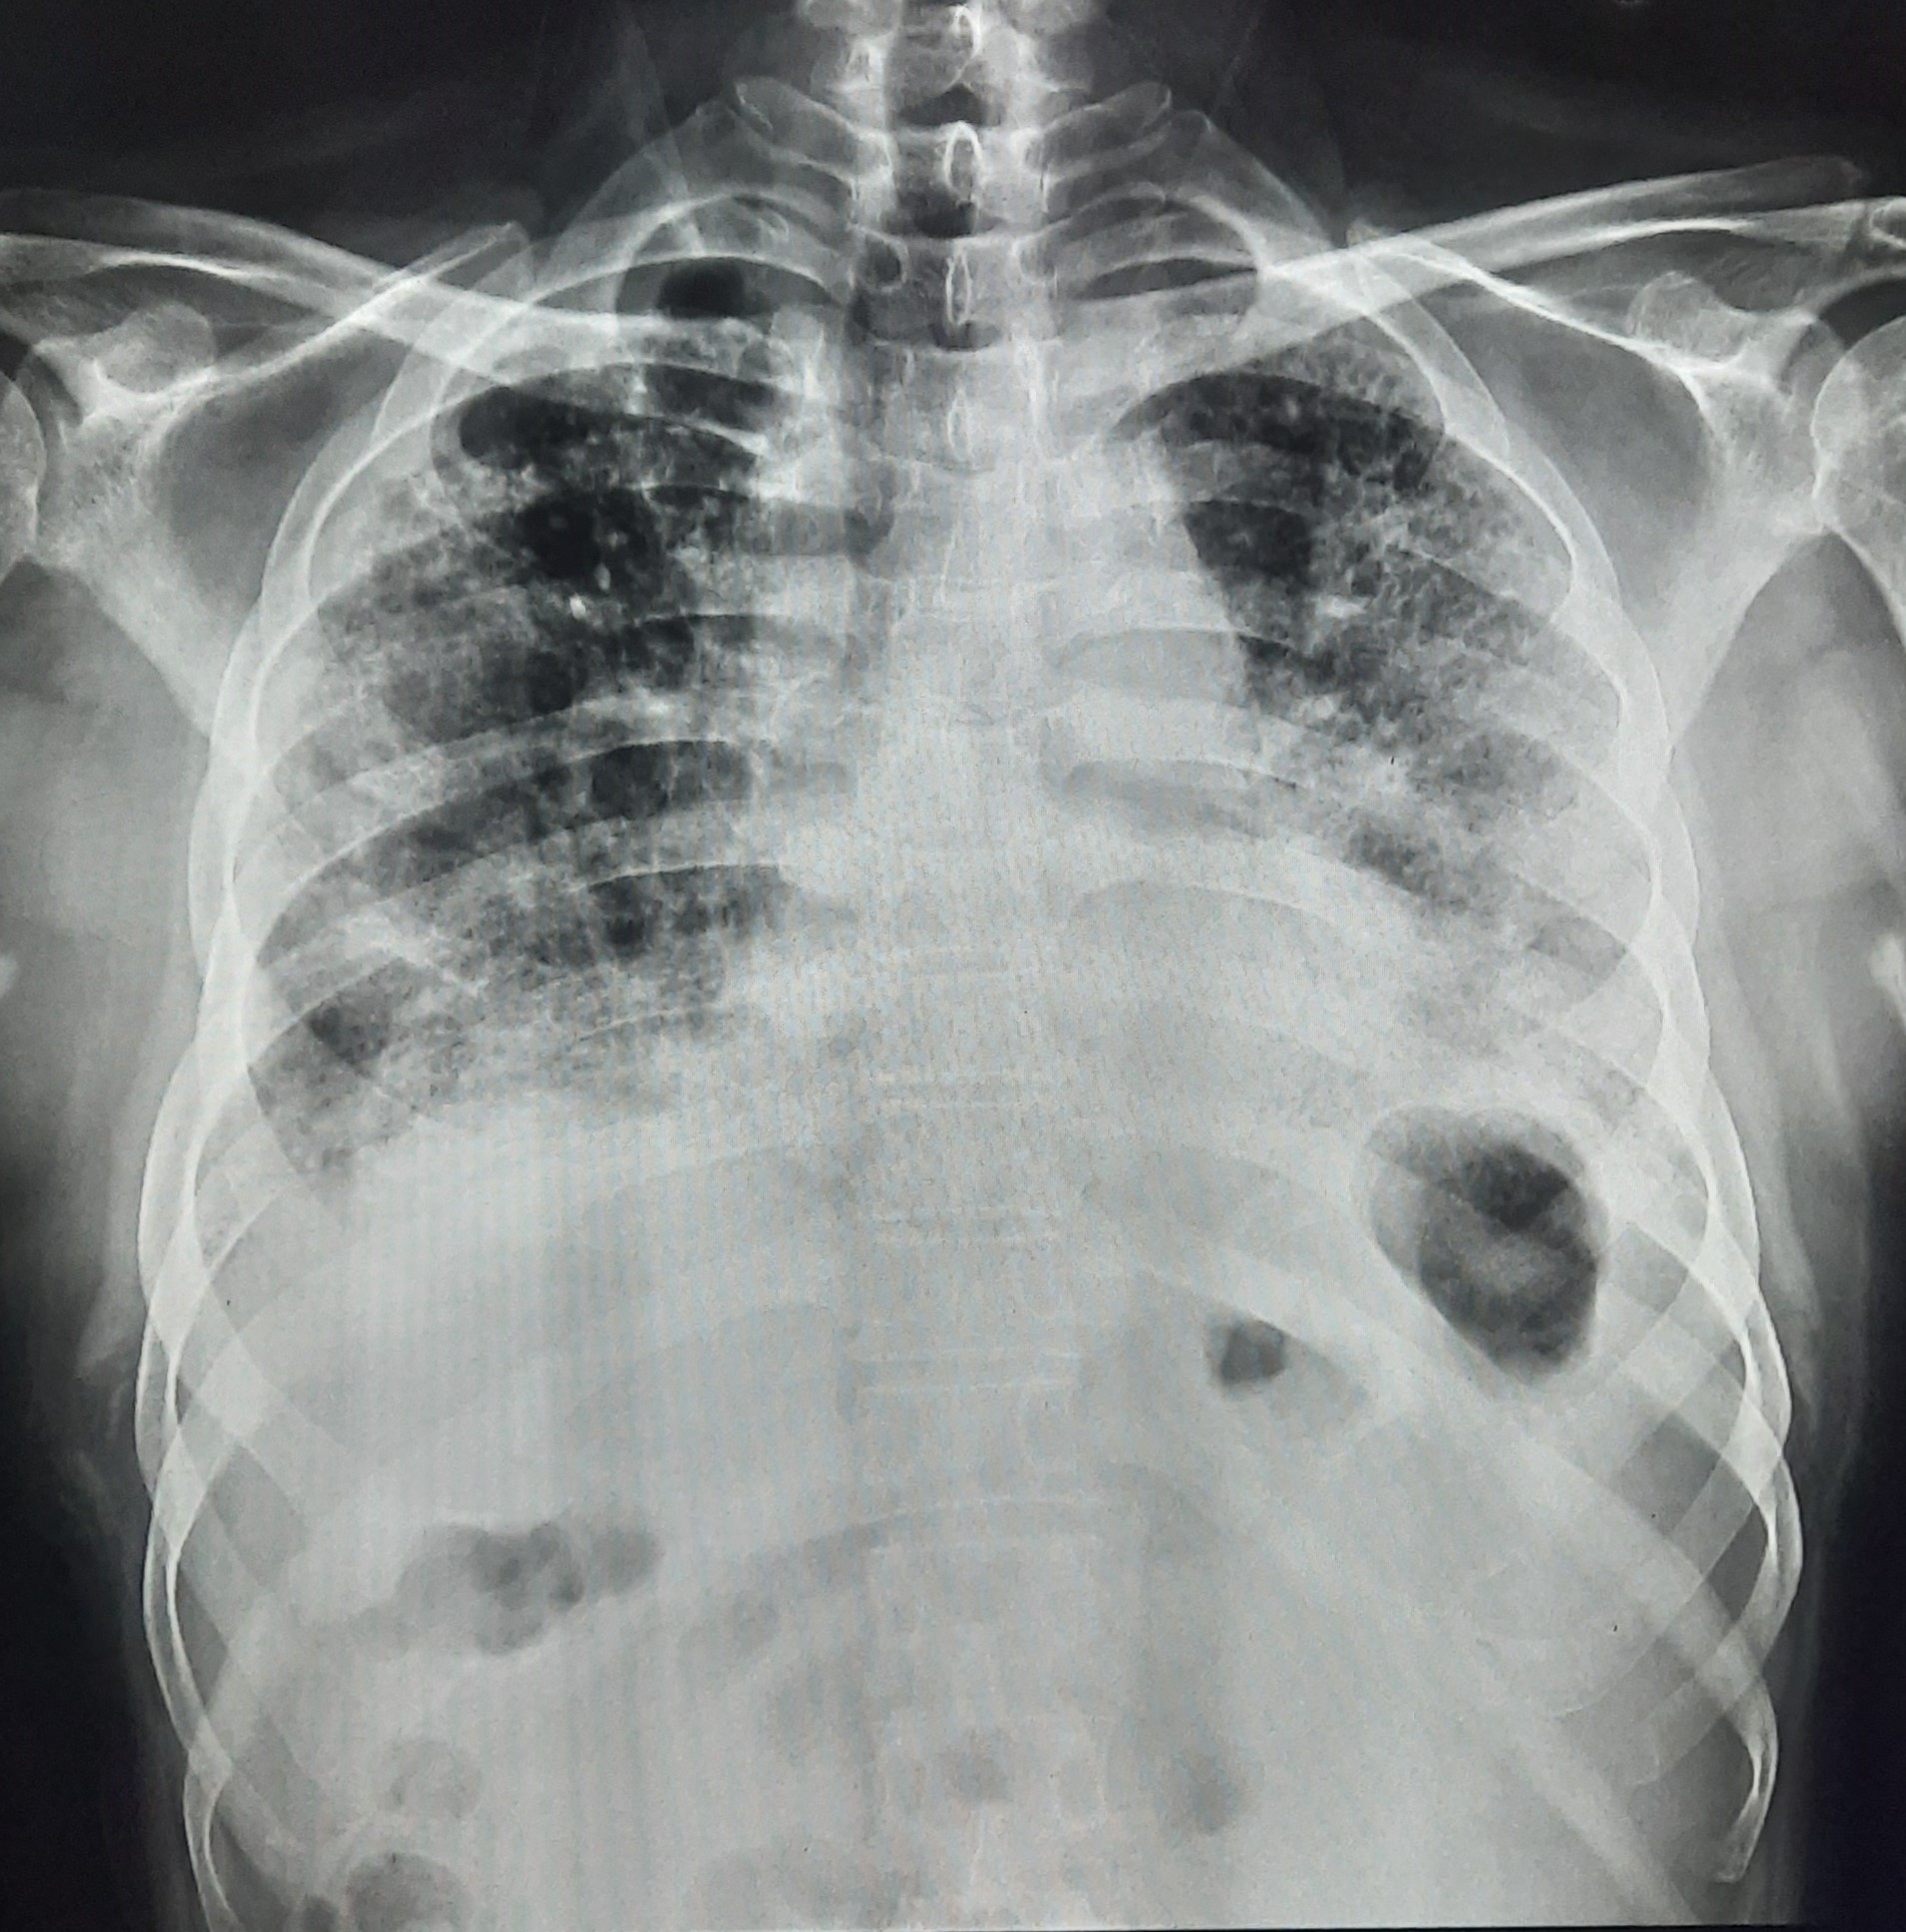

| 141 | IGGMC, Nagpur, Nagpur | P2 | 29-4331 Follow-up of 29-4023 |

Manda Barmpal Chaudhary | Consent taken on Paper | 45 Yrs. |

Provisional Diag : Disseminated TB/ Pleural Effusion With Pulmonary Infiltration

Final Diag : Right Sided Pleural Effusion With Pulmonary Infiltration |

Right CP Angle Blunting Present With Right Upper Zone/ Mid Zone Ill-Defined Opacity With Left Upper Zone Infiltration Present | ? |